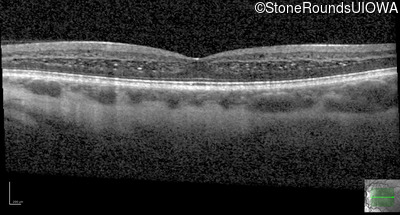

Age at visit: 26 years

This 26 year old man had significant myopia since childhood and uncorrectable reduction of acuity since his mid teens. Optic nerve abnormalities were noticed on a routine exam at age 5 and a diagnosis of Retinitis Pigmentosa was suggested. His medical history is also positive for profound hearing loss at birth and type 1 diabetes mellitus.